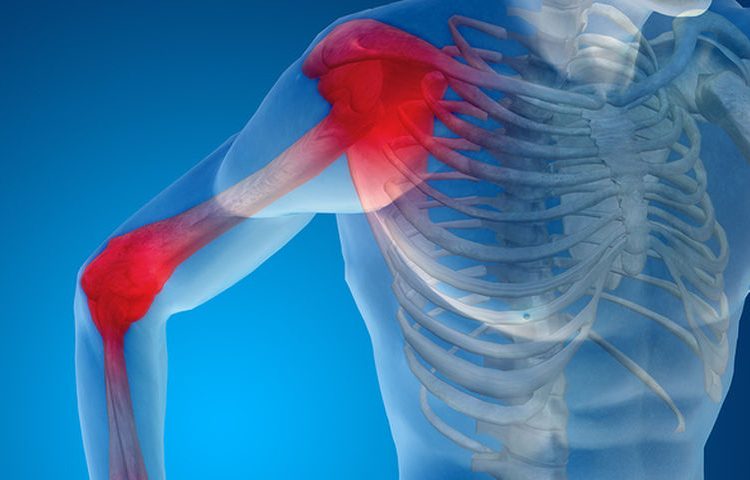

Ο παγωμένος ώμος είναι ένα σύνδρομο που εκδηλώνεται κυρίως στις ηλικίες 50-80 με έντονο πόνο στο δελτοειδή μυ του ώμου και δυσκαμψία.

Η πάθηση εκδηλώνεται σε τρία στάδια. Στο πρώτο, ο πάσχων ταλαιπωρείται επί εβδομάδες από ανεξήγητο πόνο, στο δεύτερο βιώνει επί μήνες ακραία δυσκαμψία (ο ώμος του είναι σαν να έχει κοκαλώσει) και στο τρίτο η κινητικότητα του ώμου ανακτάται σταδιακά, με αργό ρυθμό.

Δεν είναι σαφές τι ακριβώς προκαλεί τη διαταραχή στους διαβητικούς, αλλά οι επιστήμονες πιστεύουν πως με κάποιον τρόπο το περιττό σάκχαρο (γλυκόζη) συσσωρεύεται στον ώμο, συγκολλώντας τις ίνες κολλαγόνου που έχει η άρθρωση. Ως επακόλουθο της συγκόλλησης είναι ο περιορισμός της κινητικότητας της άρθρωσης.